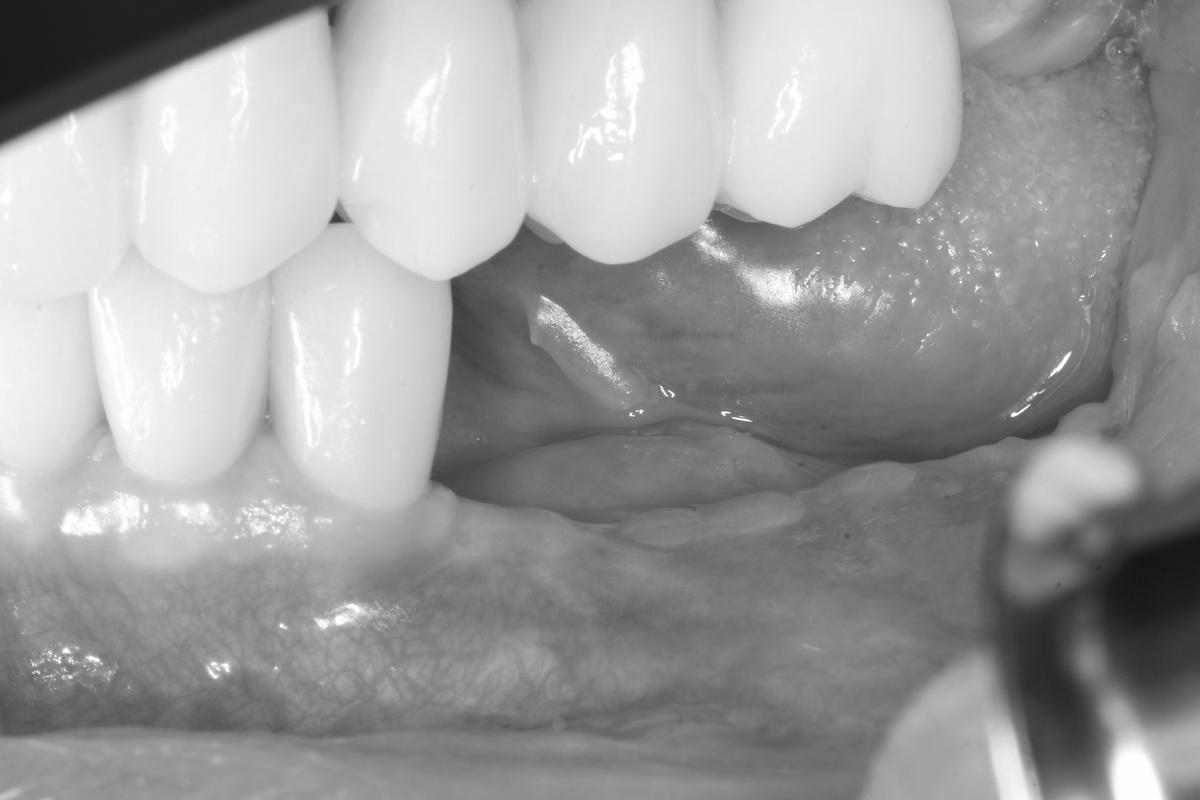

Результат спустя 1 месяц — на трёх фото ниже

Обратите внимание на то, что осталось от нижней челюсти слева. Сказать, что кости не осталось совсем — ничего не сказать

Результат вживую: